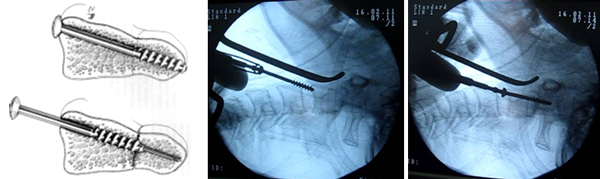

Kỹ thuật vít trực tiếp mỏm nha:

– Gây mê nội khí quản

– Tư thế cổ ưỡn vừa phải

– Rạch da đường cổ trước bên ngang mức C5, phẫu tích các lớp, đặt hệ thống vén.

– Xác định bờ dưới của thân C2

– Khoan vào bờ dưới thân C2 dưới hướng dẫn C.arms

– Hướng đi song song với thân C2 trong giới hạn của mỏm nha hướng về bờ sau đỉnh mỏm nha theo mặt phẳng đứng dọc và theo đường giữa.

– Bắt vít rỗng nòng 3.5 mm dưới hướng dẫn của kim dẫn đường và C.arms cả 2 bình diện [3].

– Đóng các lớp theo giải phẫu

– Sau mổ theo dõi sát tình trạng hô hấp của bệnh nhân trong 24h đầu.

– Cố định cổ bằng Coller cứng duy trì sau 6 tuần.

– Đánh giá lâm sàng và chẩn đoán hình ảnh sau mổ